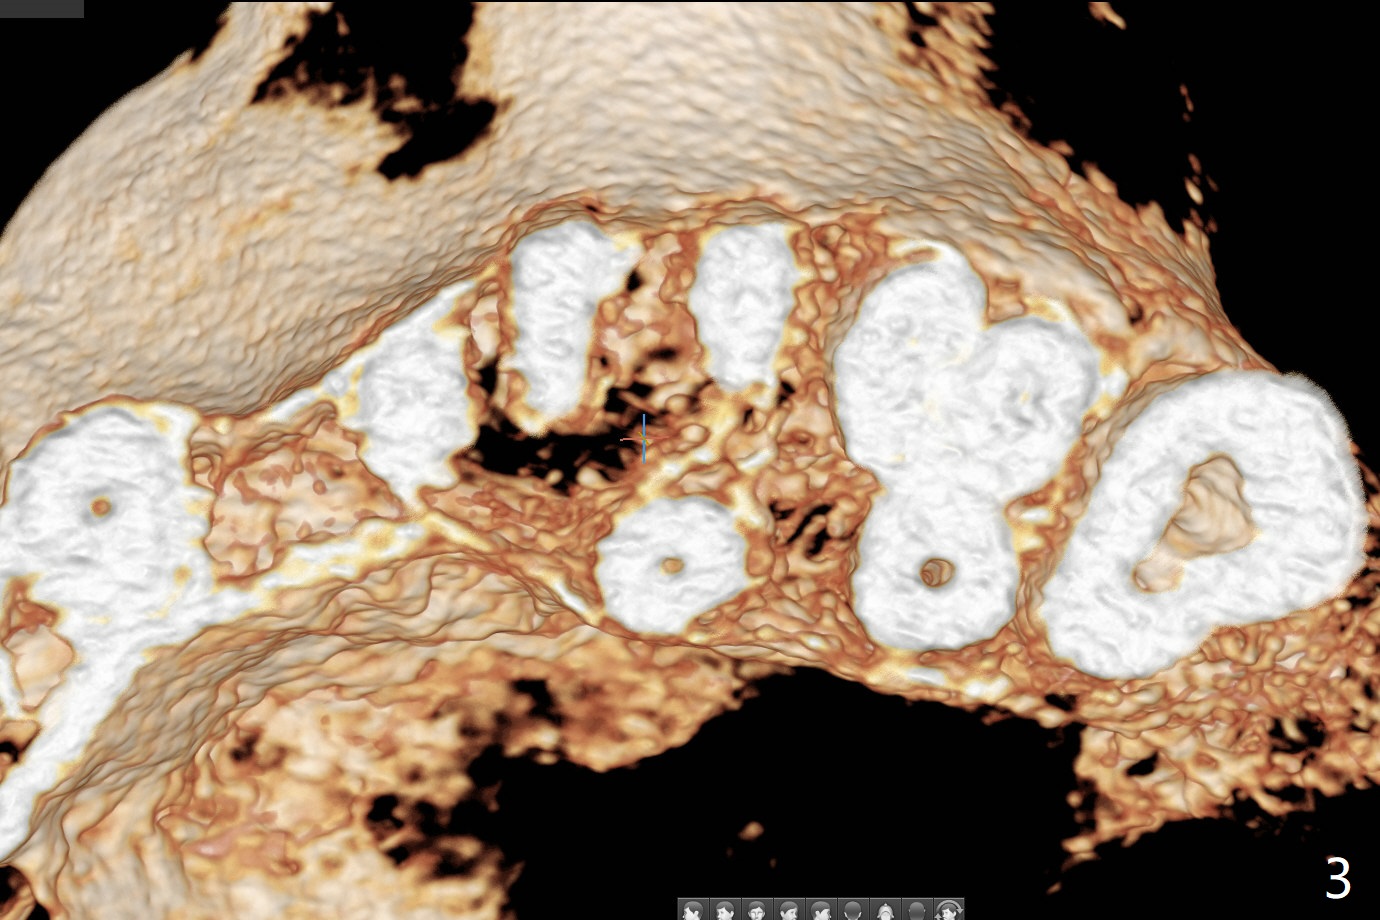

44岁女左上6远中深龋(图一:*),同意拔除种植(图二),由于近中,远中牙槽嵴不等(*),为了增加冠根比例,植体可以种浅些(箭头),但是远中多放置骨粉(红色)。为了防止钻头偏移中隔,去除牙冠(图三),保留牙根情况下,完成钻洞(图四:红色),然后拔除牙根(图五:黑色),放置植体(绿色)。